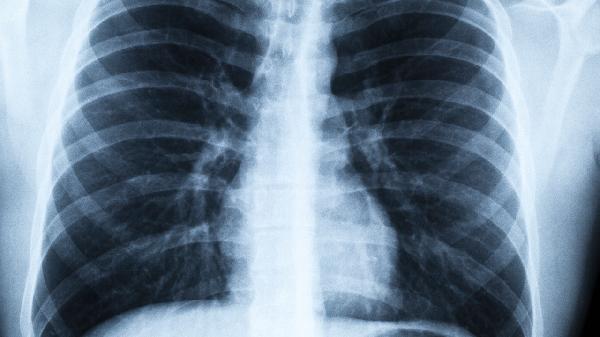

肺病患者必看:睡觉出现这3种情况,可能是病变前兆

夜深人静时,躺在床上本该是最放松的时刻,可有些人的呼吸声却像拉风箱一样沉重。这可不是简单的打呼噜,可能是肺部在发出求.救信号。肺病早期症状往往藏在这些夜间细节里,千万别当成“小毛病”就忽略了。

肺就像人体的空气净化器,当它发出异常警.报时,往往已经超负荷工作很久了。建议有上述症状的朋友,尽早做肺功能检查和胸部CT。冬季寒冷干燥,更要特别注意肺部保养,每天保证足够的饮水量,室内使用加湿器维持适宜湿度。记住,及时干预永远比事后治疗更重要。